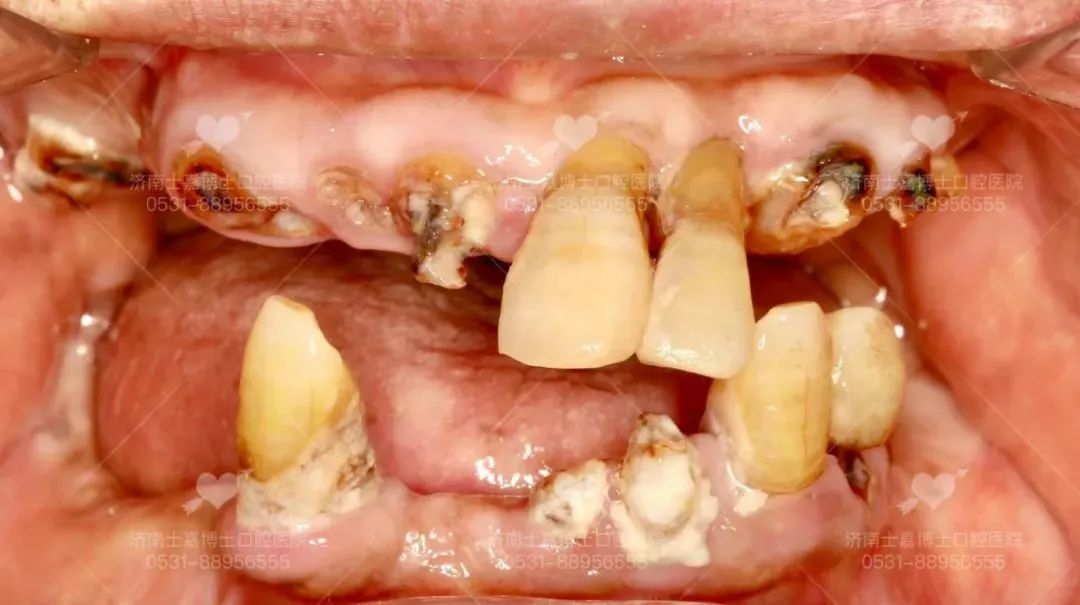

舒适化牙齿种植 告别口腔恐惧 随着人们生活水平提高,口腔健康越来越受到人们的重视,定期进行牙周保健的人群数量也在不断增长。然而,却有那么一群人,因为个人体质的原因,口腔非常敏感,咽反射严重,当口腔受到外界一丁点刺激,就会不停干呕,别说治疗了,就连普通的洁牙都无法配合医生,他们对口腔诊疗有着深深的恐惧感和特殊的需求。 济南士嘉博士口腔医院是济南卫健委审批的二级专科口腔医院,主要开展口腔种植、牙齿畸形矫正、无痛牙齿治疗、牙齿美容美白、牙周治疗、儿童牙齿及颜面部健康管理等项目,是省内首家舒适化诊疗理念的二级专科医院,舒适化儿童补牙治疗、舒适化智齿拔除治疗以及舒适化牙齿种植治疗,对于患有心脑血管病、高血压及牙科恐惧症患者而言是非常好的就诊选择,就像无痛胃镜一样,让您在无痛舒适化睡眠中完成所有口腔治疗。 给父亲的最好礼物 士嘉博士口腔医院在父亲节当天接待了这样一位患者,77岁的老先生,随着年龄不断增长,嘴里牙齿多年来一直不好,老人身体状况不是很好,有心衰,有过脑梗,本来不想接诊治疗,但是孩子的孝顺以及老人的痛苦,也确实让人心疼 父亲节当天,在儿子坚持下,决定先看一看 来到士嘉博士口腔后,经过齐鲁医院心内科及神经科会诊后,得出结论:目前老人现在情况稳定,可以耐受手术 于是,士嘉博士口腔医疗团队带头人张士杰教授和种植团队高万郝主任热情地接待了他,经检查发现: 老人种植前牙齿状况 老先生的牙齿虽然还有几颗牙齿,但上下不对称、以及残根坏牙,已经失去了正常的咀嚼功能,需要对残根坏牙和几颗牙齿进行拔除,进行即刻拔牙即刻修复即刻种植,做全口种植的治疗